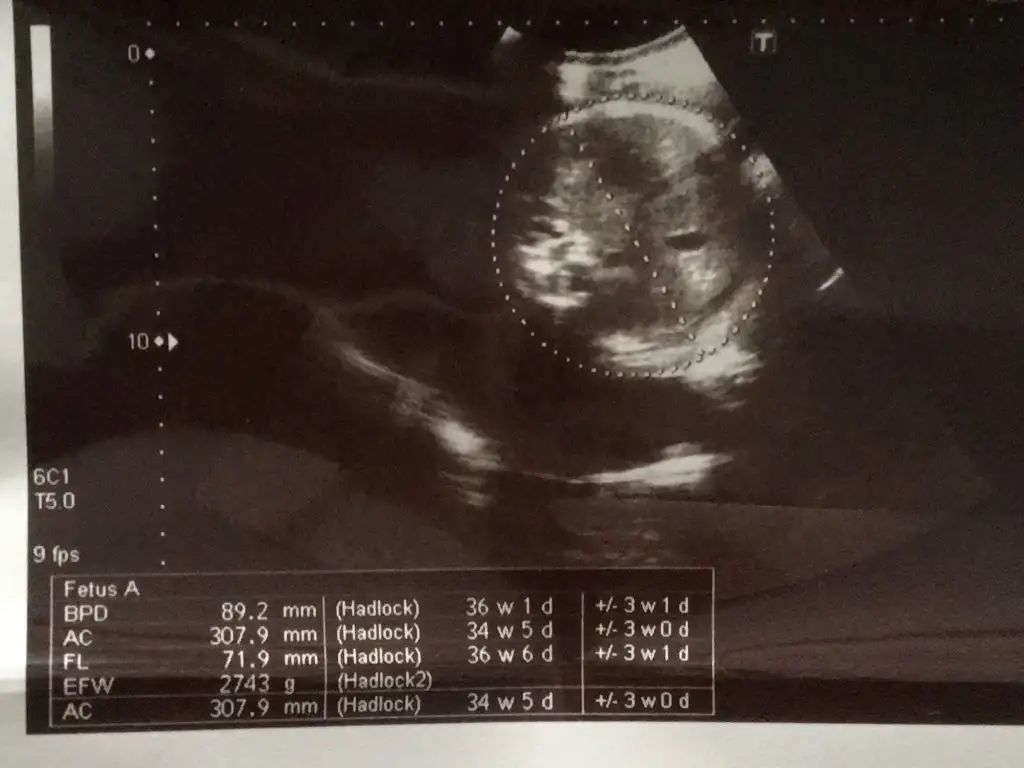

Canım benim de son iki kontrolün degerleri aynı boy ve kilo hiç ilerlememiş görünüyor. Doktora sordum son haftalarda ölçümler dogru olmuyor dediHerkese selamben sayfaya çok fazla bakamıyorum baksam bile yazılanları okuyorum cevap yazamıyorum kızlar... çok güzel doğum haberleri okudum , herkesim gözü aydın olsun darısı biz bekleyenlerin basına inşallah bugün 37+6 kontrolüm vardı ama kontrolde 37 çıktım, neyse 1 hafta oynar dedim sonra eve geldim 19 ekim de ki usg değerlerine baktım ve o günden bugüne doğru düzgün ilerleme olmadığını gördüm, sadece kilo almış bebeğim .. doktorum herşey normal bir sıkıntı yok dedi ama benim içime kurt düştü şimdi ... haftaya tekrar kontrole çağırdı ki ben artık doğum için tarih verir diyordum İlk kızım sezaryen çünkü ... gerçi bebeğim baş aşağı dönmüş ... şimdi sizden ricam eklediğim usg fotolarında haftalarına bakıp yorumlar mısınız? İlk yüklediğim 19 ekim , diğeri 4 kasım ...şimdiden hepinize teşekkür ederim